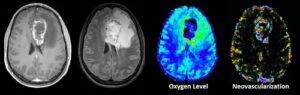

Mehr erfahren zu: "Glioblastom: Neue Methode zur Bestimmung der Prognose identifiziert" Glioblastom: Neue Methode zur Bestimmung der Prognose identifiziert Ein internationaler Forschungsverbund unter Leitung des Universitätsklinikums Hamburg-Eppendorf (UKE) hat eine neue Methode ermittelt, um die Prognose von Patienten mit Glioblastom konkreter vorherzusagen.